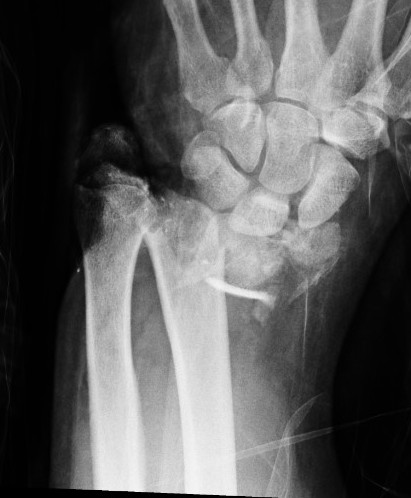

Percutaneous K Wire

Issues

Increased pin site infections

No early immobilization

Technique

Youtube K wire distal radius fracture video

Reduce fracture under anesthesia and fluoroscopy

Radial K wire

- through radial styloid

- can make small incision / blunt dissect to protect branches SRN

- cross fracture site and engage other cortex

- 1.6 or 2 mm K wire

Dorsal K wire Kapandji technique

- percutaneous by hand into fracture site

- tilt distally to reduce dorsal displacement of distal fragment

- drive into proximal radius and engage volar cortex